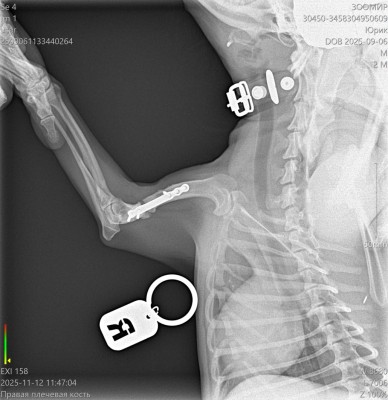

Юрик съездил сегодня на контрольный рентген.

Мозоль ОБРАЗОВАЛАСЬ. По центру она еще не очень плотная, но кость срослась.

Как Ольга паразита не оберегала, но на рентгене оказалась чуть погнутая пластина и один сломанный винт.

Снимать ничего не будем из конструкции, если не начнет отторгаться или двигаться.

2 рентгена и осмотр АН обошлись в 2600₽ ( это стоимось 2 снимков).

Юрик. Взгляд изнутри